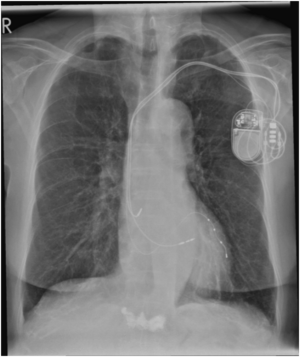

Die sogenannte Device-Therapie beinhaltet die Behandlung mit Herzschrittmachern, implantierbaren Defibrillatoren, Ereignisrekordern und anderen kardialen Stimulationssystemen.

Bei langsamen Herzrhythmusstörungen, die Leistungsminderung, Schwindel oder Bewusstlosigkeit (Synkopen) verursachen, werden Herzschrittmacher in der Regel durch einen kleinen Schnitt rechts oder links brustseitig eingesetzt und entspreche Elektroden zum Herzen geführt.

Bei Patienten, die an einer Herzschwäche leiden und ein erhöhtes Risiko für den plötzlichen Herztod haben, wird ähnlich einem Herzschrittmacher ein interner Defibrillator (ICD) implantiert. Dieser kann durch verschiedene Manöver schnelle Herzrhythmusstörungen beenden und lebensrettend sein.

Bei Patienten mit einer fortgeschrittenen Herzschwäche kann die Implantation eines Dreikammer-Schrittmachersystems (kardiale Resynchronisationstherapie = CRT) erfolgen. Diese CRT sorgt für eine gleichmäßige Erregung beider Herzkammern und kann zu einer Verringerung der Symptome der Herzschwäche, einer Optimierung der Pumpleistung und einer Verbesserung der Prognose beitragen.

Zusätzlich wird neben dem 3-Kammer-Herzschrittmacher der Reizleitungssystem-Schrittmacher (CSP, LBBA Pacing) auch hier im Agaplesion Diakonieklinikum Rotenburg angewendet:

Dabei werden die Herzschrittmachersonden direkt in das ursprüngliche Reizleitungssystem des Herzens hinein gedreht mit dem Effekt der natürlichen Erregungsausbreitung im Herzen.